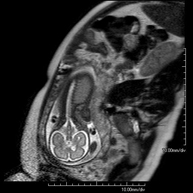

Prova diagnòstica no invasiva que consisteix en l'obtenció d'imatges d'alta definició anatòmica de l'abdomen mitjançant l'ús d'un camp electromagnètic i ones de ràdio (amb un emissor i un receptor). No utilitza radiació ionitzant. En aquesta exploració s'inclouen el fetge, el pàncrees, la melsa, la via biliar, la vesícula biliar, les glàndules suprarenals, els ronyons, l'aorta abdominal, la vena cava inferior, l'estómac, el duodè, etc. En alguns casos caldrà emprar contrast paramagnètic (Gadolini) per caracteritzar les lesions. - RM Pelvis femenina

Prova diagnòstica no invasiva que consisteix en l'obtenció d'imatges d'alta definició anatòmica de la pelvis mitjançant l'ús d'un camp electromagnètic i ones de ràdio (amb un emissor i un receptor). No utilitza radiació ionitzant. Es realitza per a l'estudi de patologies d'úter, d'ovari, de trompes i de vagina, ja siguin d'origen tumoral, inflamatori o vascular. També permet valorar les estructures adjacents localitzades a la pelvis i la identificació de les seves alteracions. De vegades és necessari l'ús de contrast intravenós (Gadolini) per caracteritzar les lesions. - RM Pelvis masculina

Prueba diagnóstica no invasiva que consiste en la obtención de imágenes de alta definición anatómica de cualquier región del cuerpo mediante el empleo de un campo electromagnético y ondas de radio (con un emisor y un receptor). No utiliza radiación ionizante. Se realiza bajo sedación con la colaboración del equipo de Anestesia. En los pacientes pediátricos es de gran ayuda porque permite realizar exploraciones sin artefactos de movimiento (lactantes, niños de corta edad, etc. en los que la situación clínica lo requiera). - RM Fetal

Prueba diagnóstica no invasiva que consiste en la obtención de imágenes de alta definición anatómica del feto en la mujer gestante mediante el empleo de un campo electromagnético y ondas de radio (con un emisor y un receptor). No utiliza radiación ionizante. Se puede realizar a partir de la semana 12 de gestación, siendo segura tanto para el feto como para la madre. Se utiliza en el caso de sospechar alguna anomalía congénita morfológica. - RM Muscular